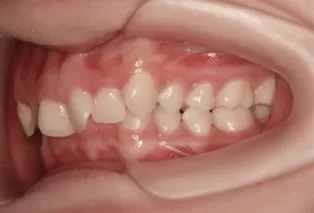

Photos intra-orales